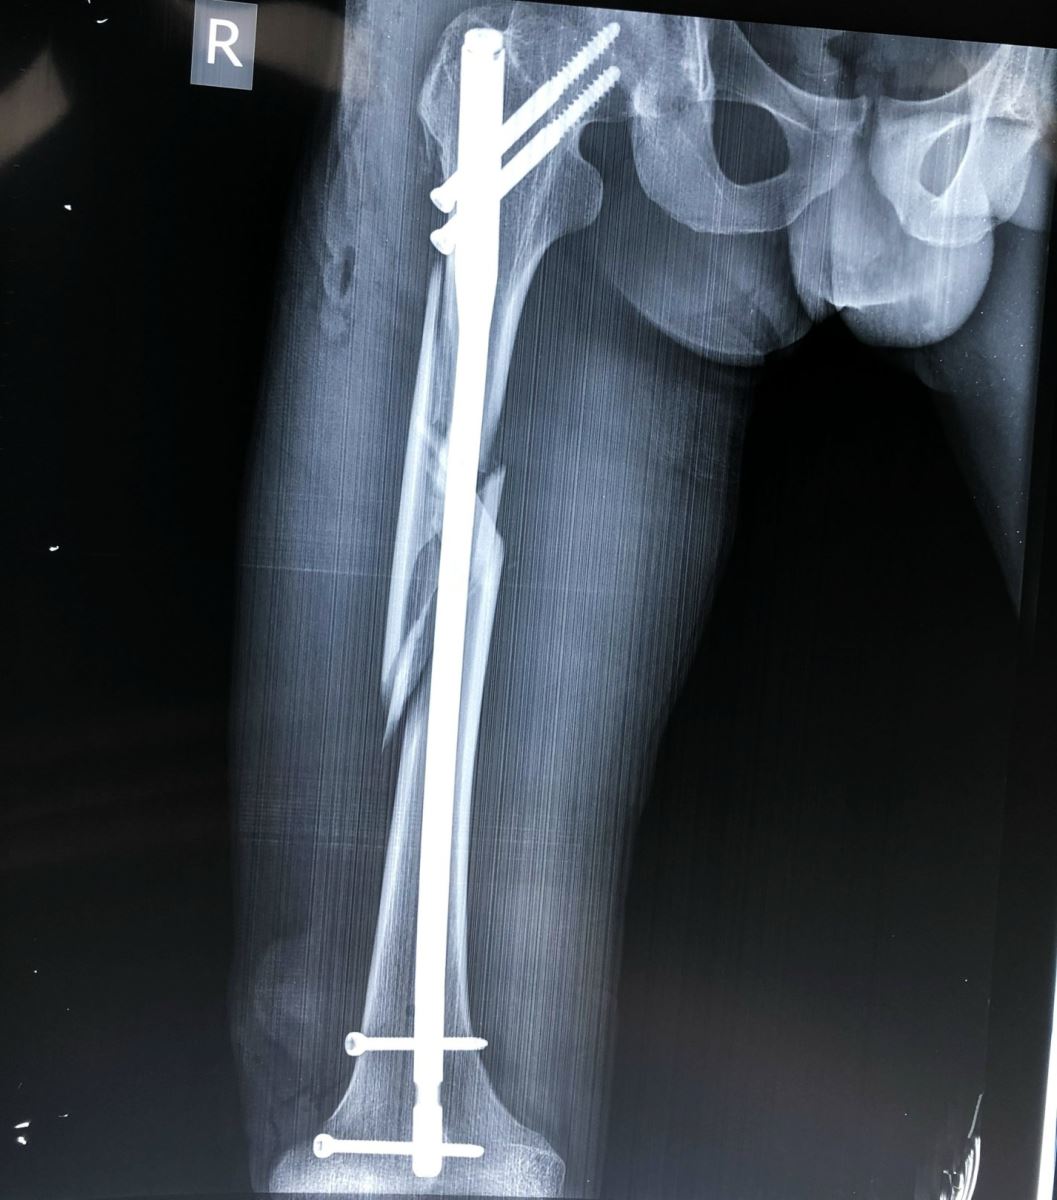

Là phương pháp điều trị hữu hiệu tích cực nhất hiện nay.

Đóng đinh nội tủy:

Áp dụng cho các trường hợp gãy thân xương đùi, tốt nhất đoạn 2/4 giữa, áp dụng trong tất cả các trường hợp gãy ngang, chéo, nhiều mảnh, gãy 2 ổ. Đóng đinh nội tủy được xem là phương pháp tốt nhất hiện nay. Nhờ màn tăng sáng, người ta đóng đinh không mở ổ gãy và có khoan rộng ống tủy. Để chống xoay của đoạn gãy xa người ta tăng cường chốt ngang qua xương. Trong trường hợp đường gãy thấp ở đoạn 1/3 giữa và dưới, có thể tiến hành đóng đinh nội tủy có chốt ngang ngược dòng từ đầu dưới xương đùi.